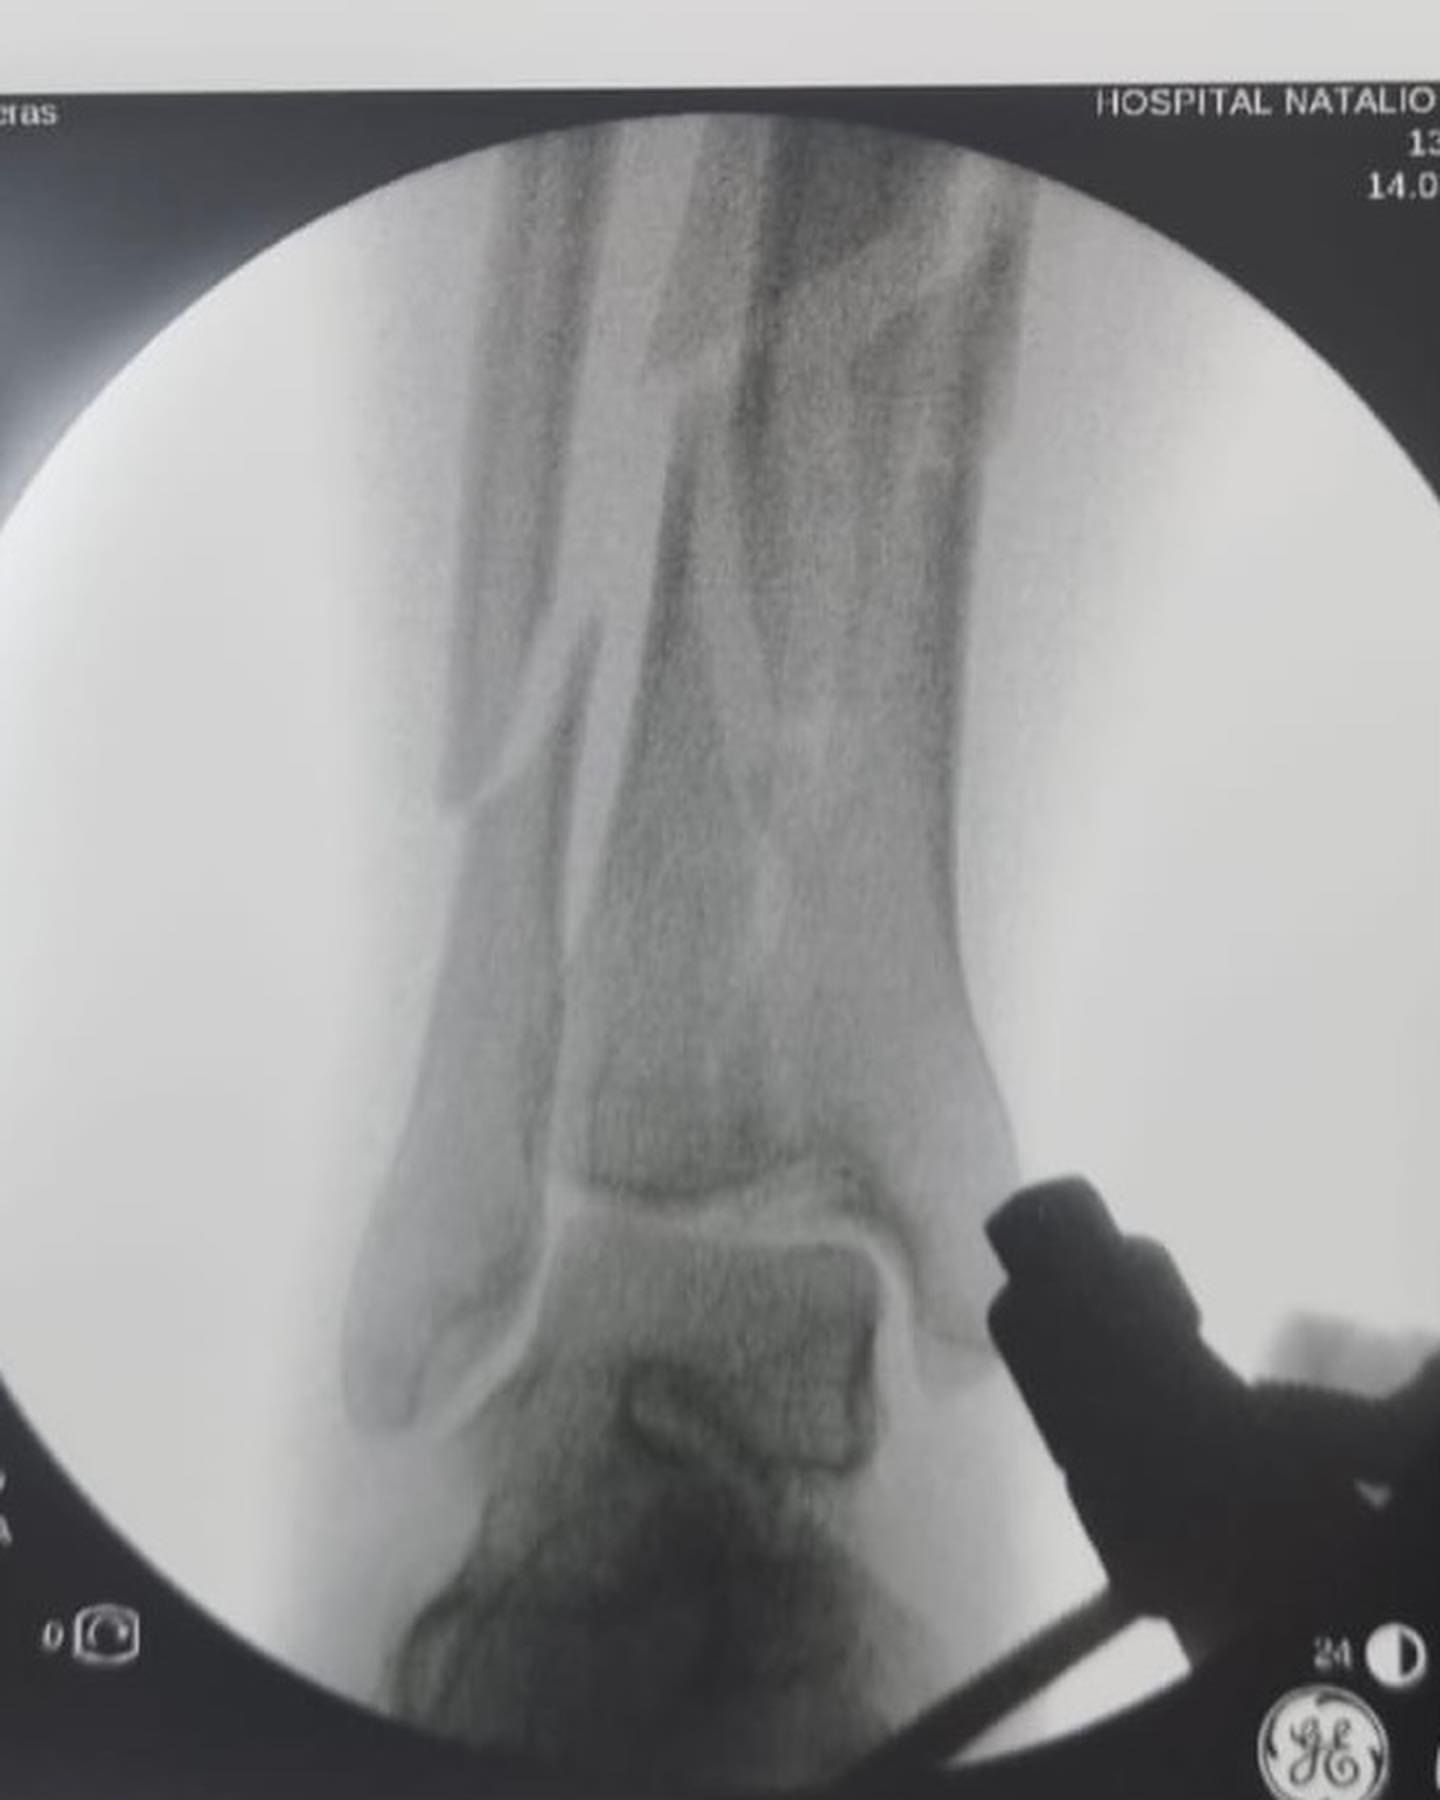

El manejo inicial de una fractura compleja de tibia representa un punto de inflexión en el proceso de recuperación del paciente. Tal como lo destacó el Dr. Escobar, la fijación externa emerge como una herramienta invaluable en esta etapa crítica.

- Estabilización inmediata: Al unir los fragmentos óseos de manera externa, se proporciona una estabilidad que reduce el dolor, disminuye el riesgo de complicaciones vasculares y nerviosas, y mejora el pronóstico de las partes blandas.

- Facilita la cirugía definitiva: La fijación externa permite abordar la fractura de manera más controlada y precisa en una segunda intervención. Al reducir el edema y la inflamación, se facilita la exposición quirúrgica y se minimizan las complicaciones intraoperatorias.